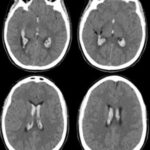

Los estudios de TC permiten evidenciar los accidentes cerebrovasculares (ACV) ocasionados por el abuso de la cocaína. Por caso, se localizó en la literatura imágenes que permiten ver el ACV isquémico agudo de la arteria cerebral media izquierda de un paciente. La TC sin contraste intravenoso visualiza la hipodensidad de la cabeza del caudado, del núcleo lenticular y de la ínsula izquierda. También se realizaron estudios de RM, que permiten observar la restricción del área isquémica en el territorio silviano(18) (ver Imagen 5).

En el caso que se viene reseñando, se realizó TC sin contraste para evidenciar eventuales daños isquémicos. En este estudio se localizó un hematoma intraparenquimatoso (ver Imagen 6). Este tipo de hematomas tiene un significativo riesgo para la persona, dado que puede avanzar hacia hemorragias con daño en la barrera hematoencefálica e incremento de la presión intracraneal, que puede ocasionar déficit neurológico e incluso la muerte.(17, 18)

En los casos de personas sin patología vascular subyacente, las hemorragias intraparenquimatosas se localizan con mayor frecuencia en los ganglios basales y el tálamo. Un caso como este se obtuvo en la literatura, correspondiente a una mujer de 23 años que sufrió una hemiplejía completa. Se le localizaron cantidades considerables de cocaína en el análisis de orina. La RM evidenció una isquemia en la rama MCA derecha con afectación de los ganglios basales(17) (ver Imagen 7).